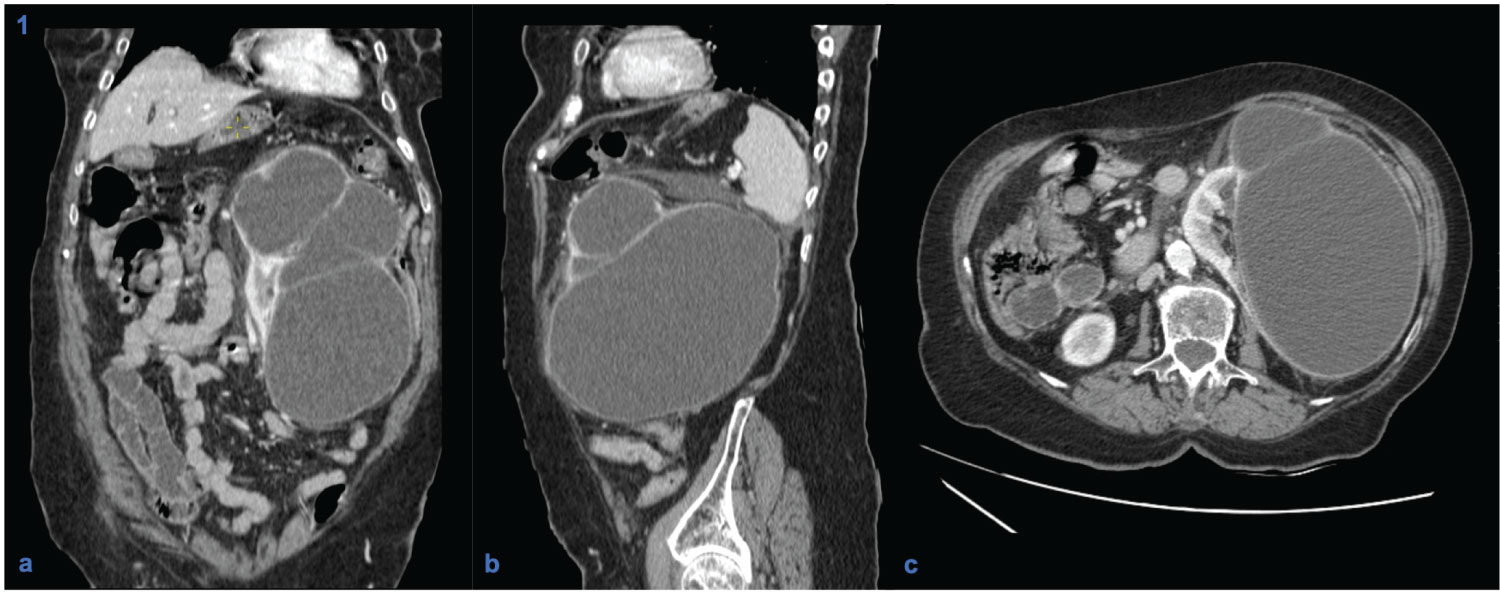

An 80-year-old woman with a history of metabolic syndrome, ischemic heart and cerebrovascular disease was admitted at the emergency department with asthenia and left abdominal and flank pain. She was on day 5th of empiric cefuroxime for urinary tract infection. On physical examination, the patient was febrile, but hemodynamically stable; an abdominal mass in the left flank was evident and painful on deep palpation; ipsilateral Murphy's sign was present. Laboratory studies showed a marked elevation of C-reactive protein (329.9 mg/L), normal renal function, and mild isolated leukocyturia (70/µL) on urinalysis. A contrast-enhanced abdominal-pelvic computed tomography scan revealed an enlarged left kidney conditioned by a multiloculated cystic lesion (14 × 11 mm in the axial plane; 21 mm in the longitudinal plane), with homogeneous content and regular parietal thickening, associated to heterogeneous densification of the left perirenal fat, without hydronephrosis (Figure 1). In the absence of unequivocal findings of complicated cyst, the diagnosis of acute pyelonephritis with failure to cephalosporin therapy (no prior urine culture) was assumed, and piperacillin/tazobactam was started. However, since the patient maintained persistent fever and elevated inflammatory markers, the possibility of occult cyst infection was considered. Thus, a percutaneous approach was performed with immediate drainage of 1500 mL of purulent content. Multisensitive K. pneumoniae and E. coli were isolated in the cystic fluid, and the antibiotic spectrum was narrowed to cefuroxime, according to the antibiogram, and drainage of the cyst was maintained through a pigtail drain (Figure 2). She evolved favorably, having completed 1 month of antibiotic and subsequently referred to Urology consultation for a potential nephrectomy.

Figure 1: Contrast-enhanced computed tomography scans (coronal (a), sagittal (b) and axial (c) planes), showing a multi-septated cystic lesion in the left kidney with wall enhancement and water-like density content, without contact with the excretory system.